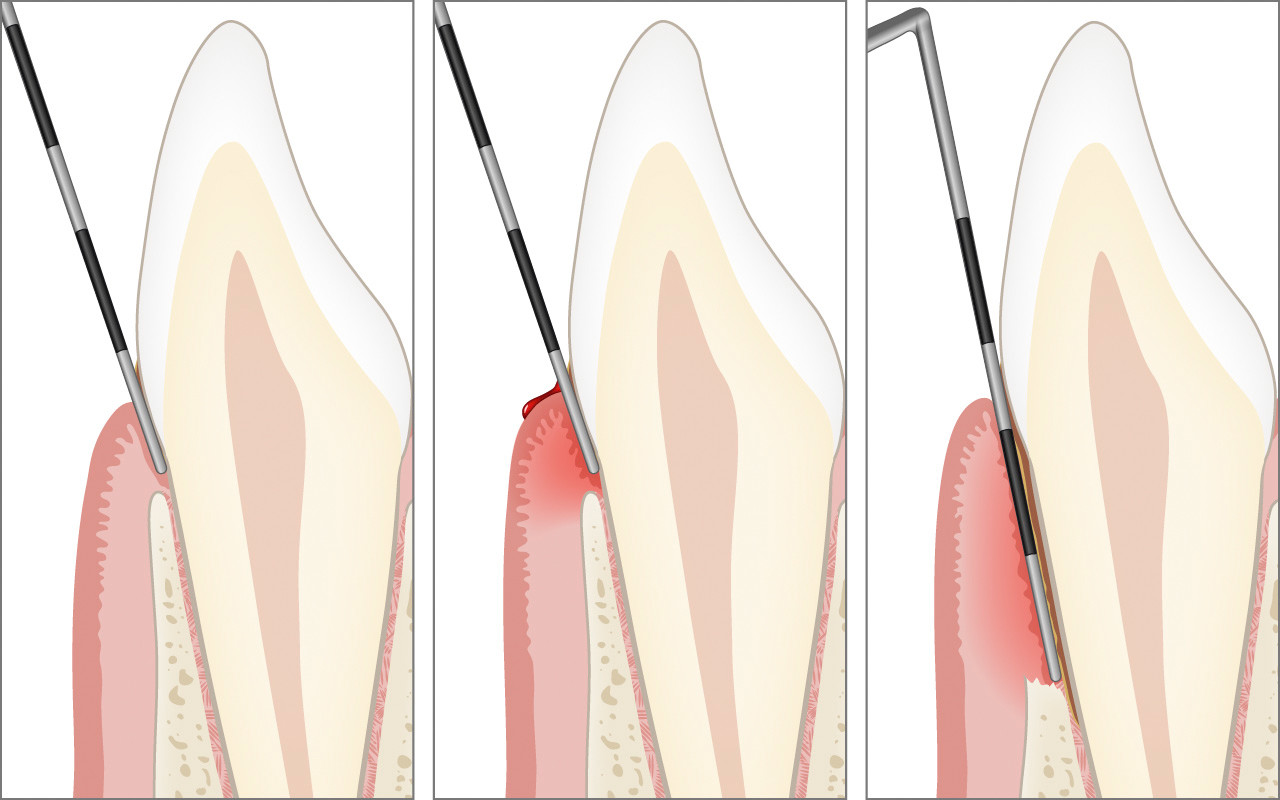

More …Die präzise klinische Sondierung mit der Parodontalsonde zur millimtergenauen Messung der Zahnfleischtaschen und der Höhe des Kieferknochens ist für die Diagnose der Parodontitis unerlässlich.

Bei einer Erstuntersuchung kann der Zahnarzt oder die Dentalhygienikerin eine so genannte parodontale Grunduntersuchung durchführen, die nur wenige Minuten dauert.

Die parodontale Grunduntersuchung dient der schnellen Feststellung, ob Zahnfleischprobleme vorliegen. Mit ihr lässt sich auf einfache Weise eine Gingivitis feststellen oder eine Parodontitis aufspüren.

Mit einer so genannten Parodontalsonde wird dabei die Tiefe des Eindringens am Zahnfleischrand sanft und präzise gemessen.

Die präzise klinische Sondierung mit der Parodontalsonde zur millimtergenauen Messung der Zahnfleischtaschen und der Höhe des Kieferknochens ist für die Diagnose der Parodontitis unerlässlich.

Bei der klinischen Untersuchung mit der Parodontalsonde wird die Eindringtiefe der Sonde in die Zahnfleischtasche an bis zu sechs Stellen pro Zahn millimetergenau gemessen. Dabei wird die Länge zwischen dem Zahnfleischrand und dem Taschenboden gemessen. Dies wird als Sondierungstiefe bezeichnet. Bei gesunden Stellen beträgt die Sondierungstiefe höchstens 3 mm. An Stellen, an denen die Parodontitis bereits zu einem Abbau der Zahnverankerung geführt hat, kann die Sondierungstiefe 4 mm oder mehr betragen.